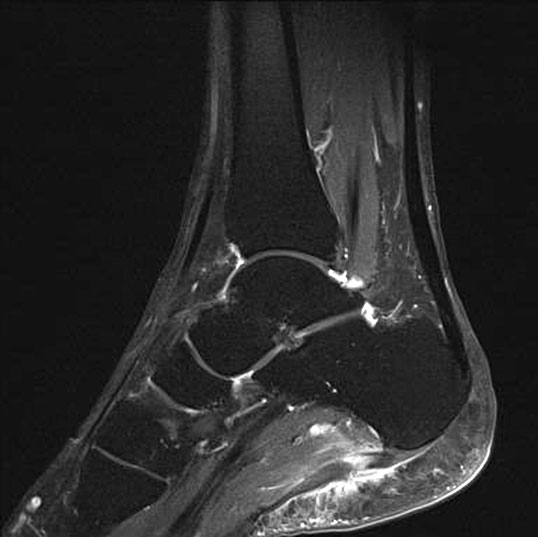

Hier befindet sich ca. 3-5 cm proximal des Tuber calcanei ein als „kritische Zone“ benannter Bezirk, der durch eine ungünstige arterielle Blutzufuhr gekennzeichnet ist (letzte Wiese). Hier finden sich häufig spindelförmige Schwellungen, die bei MRT-Diagnostik nicht selten partielle Nekrosen und Partialrupturen der Achillessehne aufweisen (Abb. 14).

Unabhängig davon können insbesondere chronische Insertionstendinosen der Achillessehne von Partialrupturen (Abb. 15) und erosiven Läsionen des dorsalen Fersenbeines begleitet sein.

Die sonographische Diagnostik eignet sich primär zur Erkennung schmerzhafter Prozesse im Verlauf der Achillessehne und kann bei Bedarf durch Röntgen bzw. MRT ergänzt werden. Besonders bei längeren Verläufen und kräftigen spindelförmigen Schwellungen (>9mm, Normwert <5mm) im Bereich der kritischen Zone sollte ein MRT zum Ausschluss von Nekrosezonen und Partialrupturen vor Therapiebeginn veranlasst werden. Die sonographisch leicht zu erfassende Veränderung der Sehnendicke im mittleren Sehnenanteil ist ein guter Indikator für die Schwere der Erkrankung und die Beurteilung des Behandlungsverlaufes. Die sichtbaren Veränderungen am distalen knöchernen Ansatz der Sehne sind diskreter.

Insbesondere bei größeren Partialrupturen (Abb. 14) sollten operative Verfahren erörtert werden. Kleinere Partialrupturen sind der ESWT gut zugänglich, wie die beiden nachfolgenden Beispiele zeigen:

In Abhängigkeit des Befundes kann die Verwendung eines Vacoped-Stiefels für die Zeit der Therapie sinnvoll sein. Eine MRT-Kontrolle nach Therapie einer Partialruptur kann nach 5-6 Monaten durchgeführt werden.